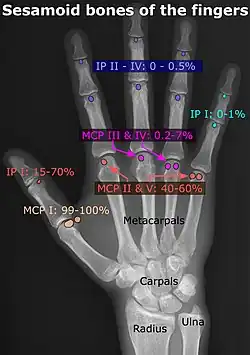

- Location and structure: Erica Chu, Donald Resnick (June 2014). "MRI Web Clinic — June 2014: Sesamoid Bones: Normal and Abnormal". Radsource: PACS Radiology Systems. Retrieved 2017-11-04.

- Prevalences: Chen W; Cheng J; Sun R; Zhang Z; Zhu Y; Ipaktchi K; et al. (2015). "Prevalence and variation of sesamoid bones in the hand: a multi-center radiographic study". Int J Clin Exp Med. 8 (7): 11721–6. PMC 4565393. PMID 26380010. - ^ "Poster Abstracts" (PDF). Association for Sports Medicine of Serbia (Udruženje za medicinu sporta Srbije). 2006. Retrieved 2017-11-03., citing: Natsis K.; Beletsiotis A.; Terzidis I.; Gigis P. "A study of the accessory bones of the foot. Incidence in the Greek population-clinical significance" (PDF).